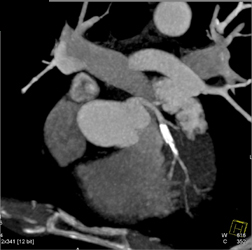

Diagnosis

Patent LAD Stent